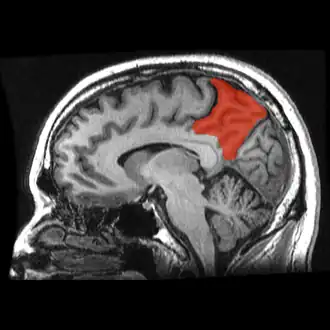

![]() Sagittal MRI slice with the precuneus shown in red. (Anterior to the left.) | |

In neuroanatomy, the precuneus is the portion of the superior parietal lobule on the medial surface of each brain hemisphere. It is located in front of the cuneus (the upper portion of the occipital lobe). The precuneus is bounded in front by the marginal branch of the cingulate sulcus, at the rear by the parieto-occipital sulcus, and underneath by the subparietal sulcus. It is involved with episodic memory, visuospatial processing, reflections upon self, and aspects of consciousness.